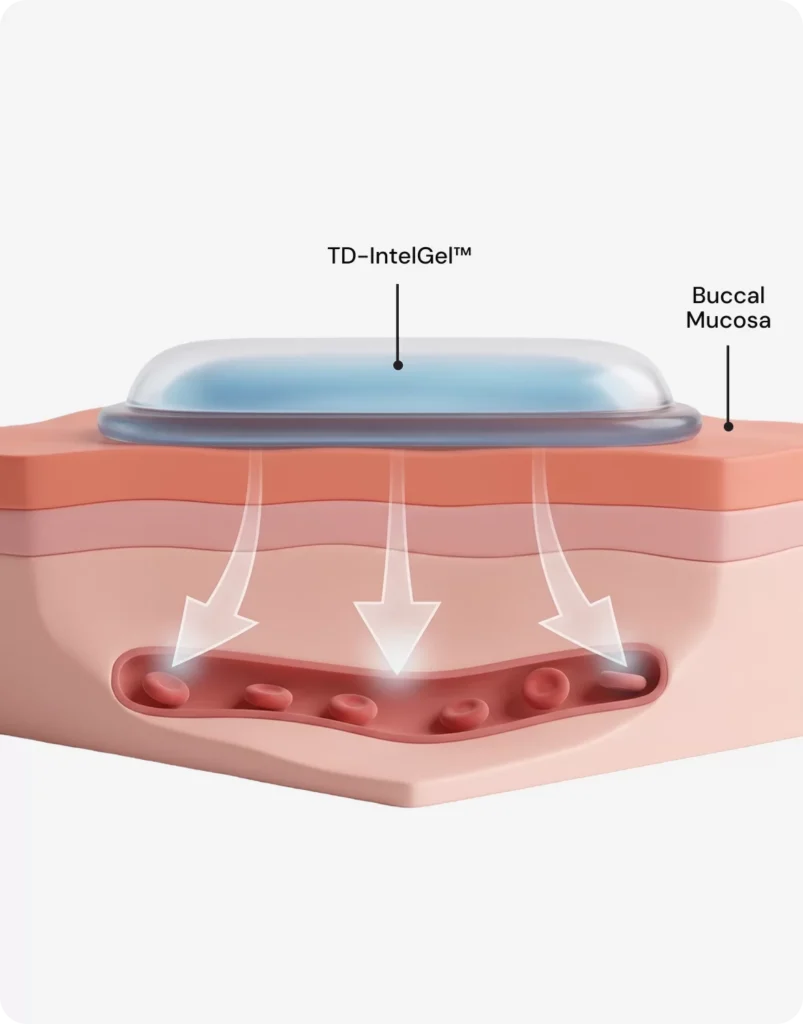

3

SmartSeal Barrier

Muco-SmartSeal® technology creates a secure peripheral seal preventing peptide leakage into saliva and minimizing washout into gastrointestinal tract for targeted absorption

4

Non-Invasive Uptake

Provides painless, needle-free delivery bypassing gastrointestinal breakdown and first-pass liver metabolism, enabling convenient and effective systemic peptide administration through buccal route